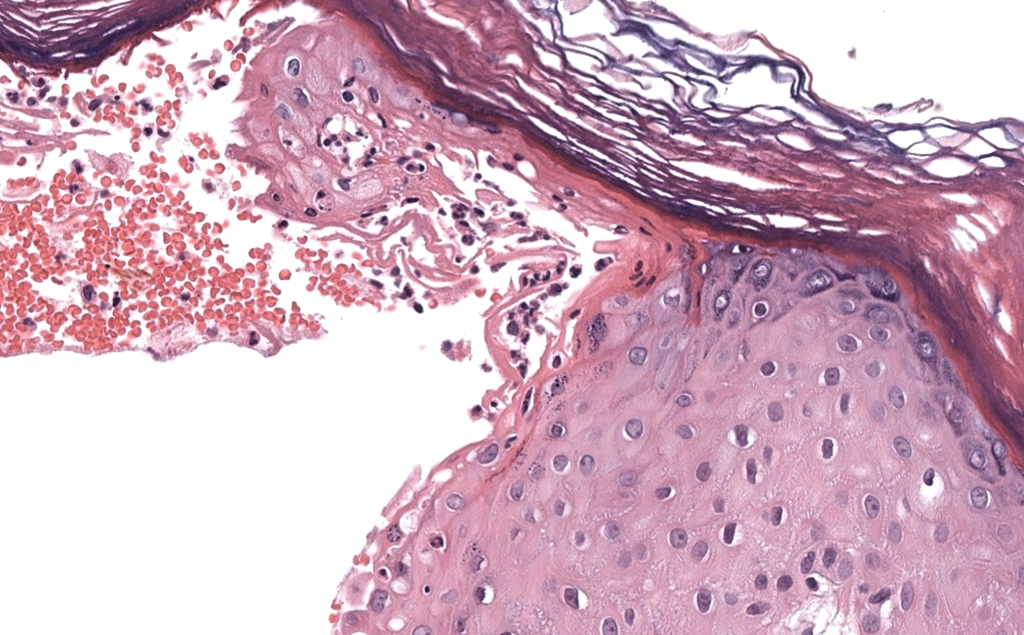

- Histología necesaria

- Biopsia de pústula reciente con gran pústula subcórnea neutrofílica.

- Ausencia de hiperplasia psoriasiforme típica y de vasculitis franca.

- Tinciones especiales negativas para hongos y bacterias significativas.